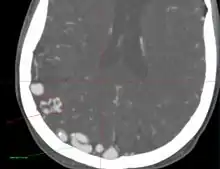

- Originally described by Luschka and Virchow in the mid 1800s, AVMs are abnormal communications between arteries and veins without the normal capillary flow.

- Abnormal communication between artery and vein, with disproportionate and unbalanced hydrodynamic stress across them. The direct connection between the arterial and venous systems exposes the venous system to abnormally high pressures and results in the formation of enlarged feeding vessels and enlarged draining venous structures.

- Point of abnormal communication is known as the nidus

- Hemorrhage is the most common reason for presentation (~50%). It is often associated with the acute onset of a severe headache that may be described as “the worst headache of my life”. Depending on the location, it may also be associated with a new neurologic deficit. Seizure can be seen in about 45% of patients, headache in 33%, and neurologic deficit in 20%.